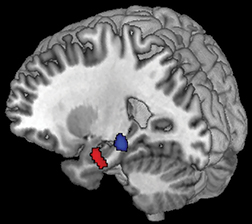

"I nostri risultati suggeriscono che se una piccola area di cellule cerebrali, chiamata «area tegmentale ventrale», non produce la giusta quantità di dopamina per l'ippocampo, un piccolo organo situato nel lobo temporale del cervello, quest'ultimo non funzionerà in modo efficiente.

"L'ippocampo è associato alla formazione di nuovi ricordi, quindi questi risultati sono cruciali per la diagnosi precoce del MA. I risultati indicano un cambiamento che avviene molto presto, che potrebbe innescare la malattia.

I risultati hanno mostrato un collegamento chiave tra la dimensione e la funzione dell'area tegmentale ventrale, la dimensione dell'ippocampo e la capacità di apprendere nuovi materiali.